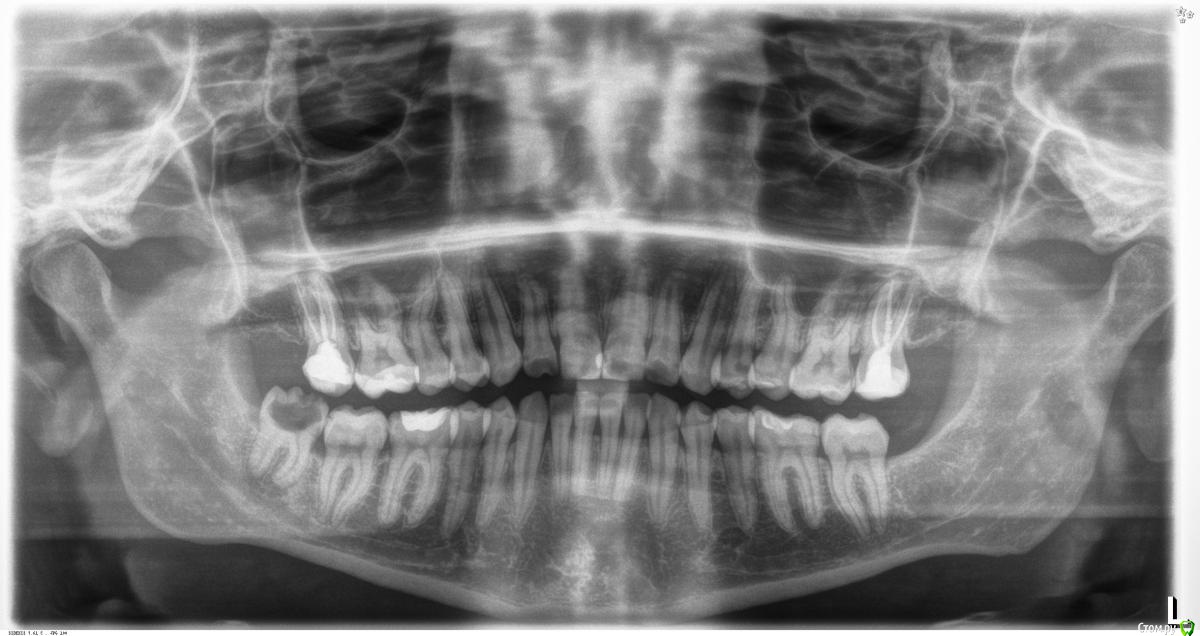

Pan Опубликовано 6 мая, 2017 Поделиться Опубликовано 6 мая, 2017 (изменено) типичная локализация кариеса при плохой гигиене и злоупотреблении в питании фастфуда. Ну понятно, что всё это на фоне сниженной кариесрезистентности. Первым делом нужно объяснить девушке значимую роль питания и гигиены в развитии кариозных процессов. Изменено 6 мая, 2017 пользователем Pan 1 Ссылка на комментарий

inSight Опубликовано 9 мая, 2017 Поделиться Опубликовано 9 мая, 2017 (изменено) С чего начинать обследование, к кому направлять на консультацию? И собственно как вести дальше? Эндокринолог, анамнез на хрон заболевания, пародонтитом (пугал бы, и пробывал бы на проф гигиене вести как писали ранее "фуксином пополоскать,чтобы наглядно было" от такого пациенты начинают чистить, т.к уходят с прокрашенными зубами), прикус(ортопед), тем временем пульпит лечил бы. Изменено 9 мая, 2017 пользователем inSight Ссылка на комментарий

St. Опубликовано 9 мая, 2017 Поделиться Опубликовано 9 мая, 2017 Принесла анализы и заключения специалистов.как оказалось пару месяцев назад обследовалась. Практически космонавт)) Слегка увеличена щитовидка, но гормоны в норме. Газировку и фреши не пьет, фастфуд не ест. Так ничего не беспокоит кроме внешнего вида.Озвучили вариант терапевтического лечения сиц+рем.терапия ивариант тотала, ушла думать.Как думаете тотал может решить вопрос или есть высокая вероятность вторичного поражения? Ссылка на комментарий